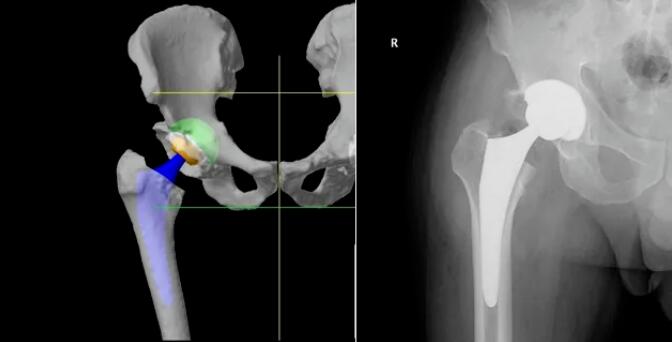

机械臂、导航模块和摄像立架是Mako机器人的核心组成部分,它们犹如人的“手臂”、“大脑”和“眼睛”,将传统的手动手术过程转化为数字化规划,通过“术前完整的手术规划”、“术中1度和1毫米的精准截骨与假体植入”,实现人工关节的高精度植入,使其完美适配人体关节的生理结构与活动需求,达成“精准微创、加速康复”的治疗目标。

利用患者术前CT数据构建3D骨骼模型,通过导航模块在专属3D模型图像上规划植入物尺寸与摆放位置,对安装效果和截骨量、截骨角度等进行提前“预演”,实现精准术前方案定制。

借助限制性立体定位边界与三维可视化截骨界面,独有的反馈式机器臂辅助医生实现精准截骨与假体精准安放。患者不仅恢复更快、使用体验更佳,同时有效降低磨损率与并发症,延长假体使用寿命,让“一次置换用终生”成为可能!

相较于传统关节置换手术依赖医生个人经验、存在假体定位欠佳与术后并发症风险等问题,Mako智能手术机器人辅助置换,为医生的操作精准度和患者的术后恢复带来了突破性进步。从“经验主导”到“智能精准”,每一台手术都以严苛标准执行,大幅降低手术风险,缩短康复周期。